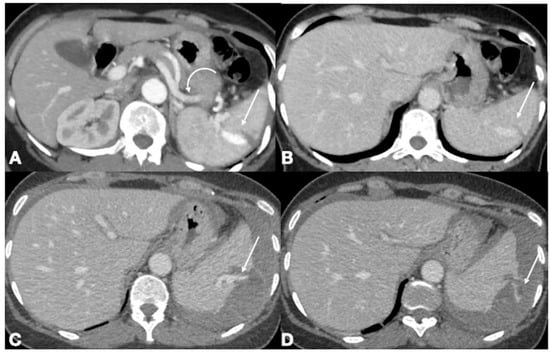

- Iacobellis, F.; Scaglione, M.; Brillantino, A.; Scuderi, M.G.; Giurazza, F.; Grassi, R.; Noschese, G.; Niola, R.; Al Zuhir, N.Y.S.; Romano, L. The additional value of the arterial phase in the CT assessment of liver vascular injuries after high-energy blunt trauma. Emerg. Radiol. 2019, 26, 647–654. [Google Scholar] [CrossRef]

- Iacobellis, F.; Ierardi, A.M.; Mazzei, M.A.; Biasina, A.M.; Carrafiello, G.; Nicola, R.; Scaglione, M. Dual-phase CT for the assessment of acute vascular injuries in high-energy blunt trauma: The imaging findings and management implications. Br. J. Radiol. 2016, 89, 20150952. [Google Scholar] [CrossRef]

- Romano, L.; Giovine, S.; Guidi, G.; Tortora, G.; Cinque, T.; Romano, S. Hepatic trauma: CT findings and considerations based on our experience in emergency diagnostic imaging. Eur. J. Radiol. 2004, 50, 59–66. [Google Scholar] [CrossRef]

- Coccolini, F.; Panel, T.W.E.; Coimbra, R.; Ordonez, C.; Kluger, Y.; Vega, F.; Moore, E.E.; Biffl, W.; Peitzman, A.; Horer, T.; et al. Liver trauma: WSES 2020 guidelines. World J. Emerg. Surg. 2020, 15, 24. [Google Scholar] [CrossRef]